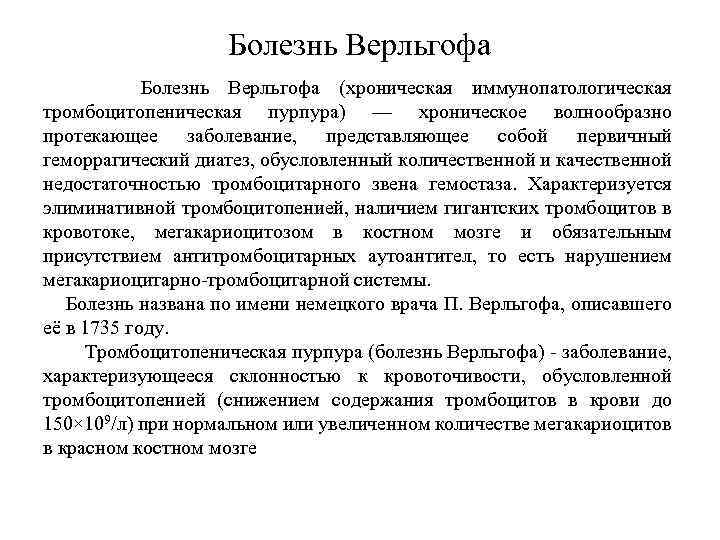

Болезнь Верльгофа (хроническая иммунопатологическая тромбоцитопеническая пурпура) — хроническое волнообразно протекающее заболевание, представляющее собой первичный геморрагический диатез, обусловленный количественной и качественной недостаточностью тромбоцитарного звена гемостаза. Характеризуется элиминативной тромбоцитопенией, наличием гигантских тромбоцитов в кровотоке, мегакариоцитозом в костном мозге и обязательным присутствием антитромбоцитарных аутоантител, то есть нарушением мегакариоцитарно-тромбоцитарной системы. Болезнь названа по имени немецкого врача П. Верльгофа, описавшего её в 1735 году. Тромбоцитопеническая пурпура (болезнь Верльгофа) - заболевание, характеризующееся склонностью к кровоточивости, обусловленной тромбоцитопенией (снижением содержания тромбоцитов в крови до 150× 109/л) при нормальном или увеличенном количестве мегакариоцитов в красном костном мозге